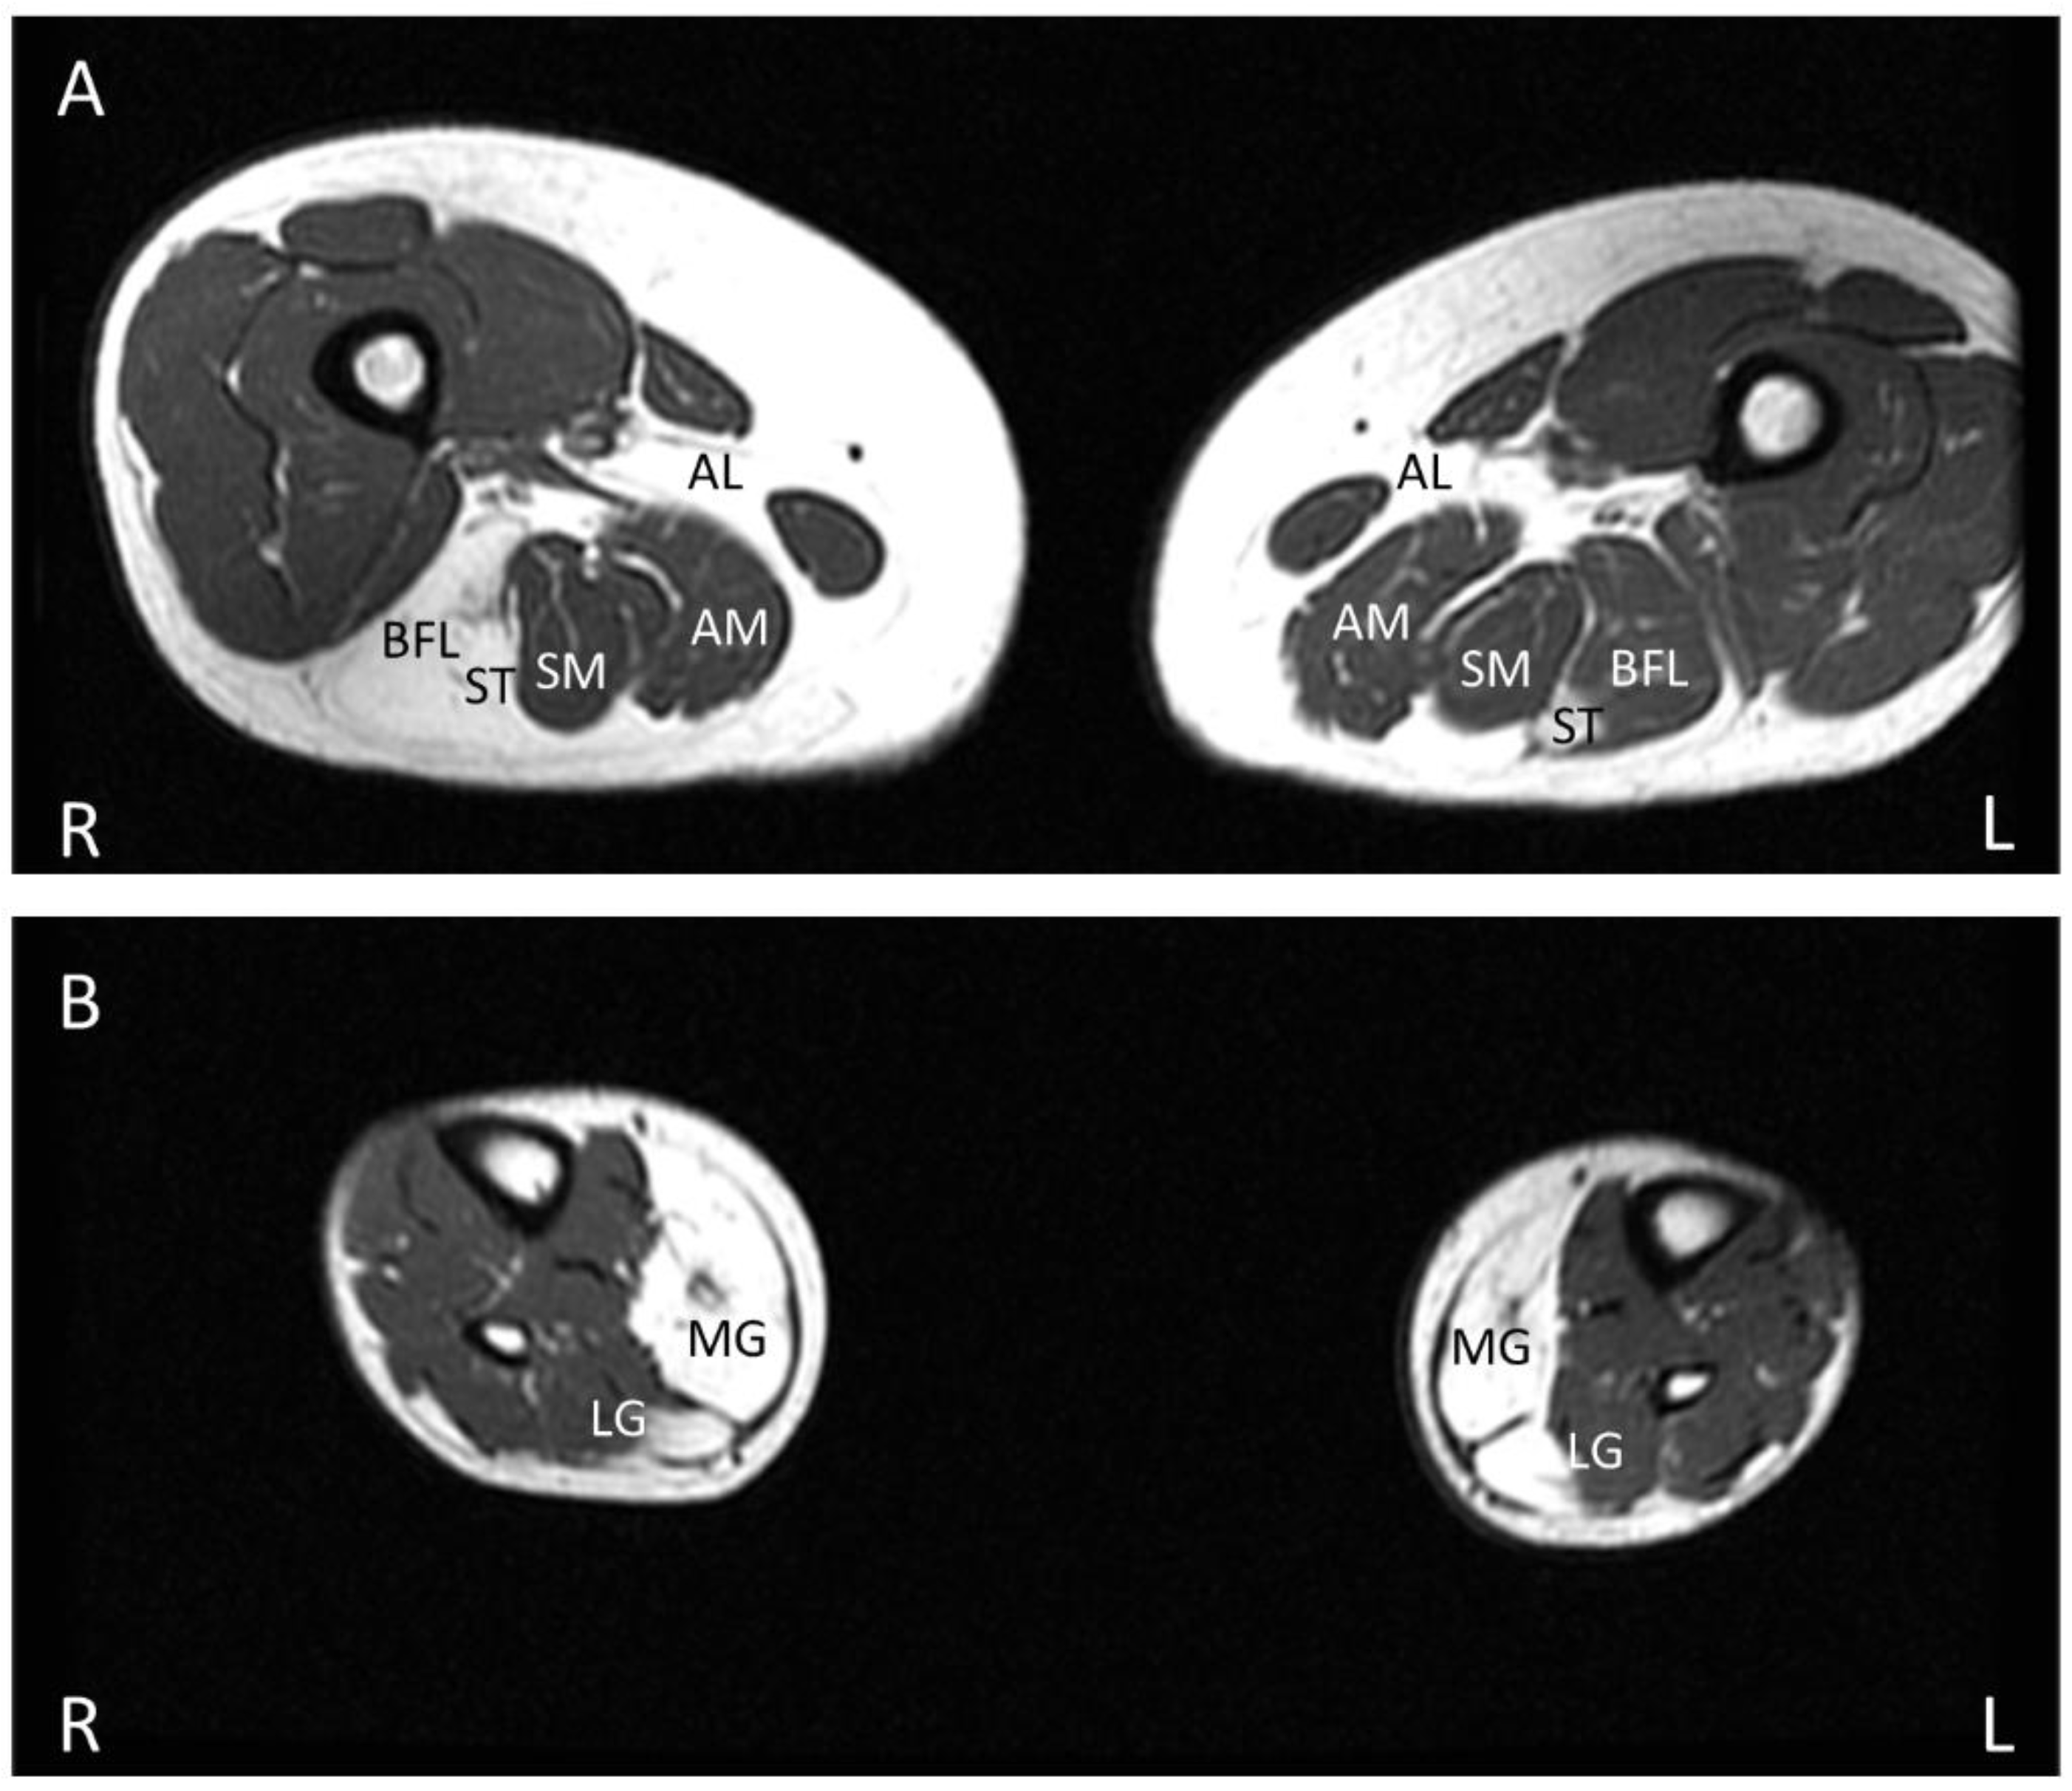

8. Muscle MRI

- Khawajazada, T.; Kass, K.; Rudolf, K.; de Stricker Borch, J.; Sheikh, A.M.; Witting, N.; Vissing, J. Muscle involvement assessed by quantitative magnetic resonance imaging in patients with anoctamin 5 deficiency. Eur. J. Neurol. 2021, 28, 3121–3132. [Google Scholar] [CrossRef] [PubMed]

- Mahjneh, I.; Bashir, R.; Kiuru-Enari, S.; Linssen, W.; Lamminen, A.; Visser, M. Selective pattern of muscle involvement seen in distal muscular dystrophy associated with anoctamin 5 mutations: A follow-up muscle MRI study. Neuromuscul. Disord. NMD 2012, 22 (Suppl. S2), S130–S136. [Google Scholar] [CrossRef]

- Sarkozy, A.; Deschauer, M.; Carlier, R.Y.; Schrank, B.; Seeger, J.; Walter, M.C.; Schoser, B.; Reilich, P.; Leturq, F.; Radunovic, A.; et al. Muscle MRI findings in limb girdle muscular dystrophy type 2L. Neuromuscul. Disord. NMD 2012, 22 (Suppl. S2), S122–S129. [Google Scholar] [CrossRef] [PubMed]

- Holm-Yildiz, S.; Witting, N.; de Stricker Borch, J.; Kass, K.; Khawajazada, T.; Krag, T.; Vissing, J. Muscle biopsy and MRI findings in ANO5-related myopathy. Muscle Nerve 2021, 64, 743–748. [Google Scholar] [CrossRef] [PubMed]